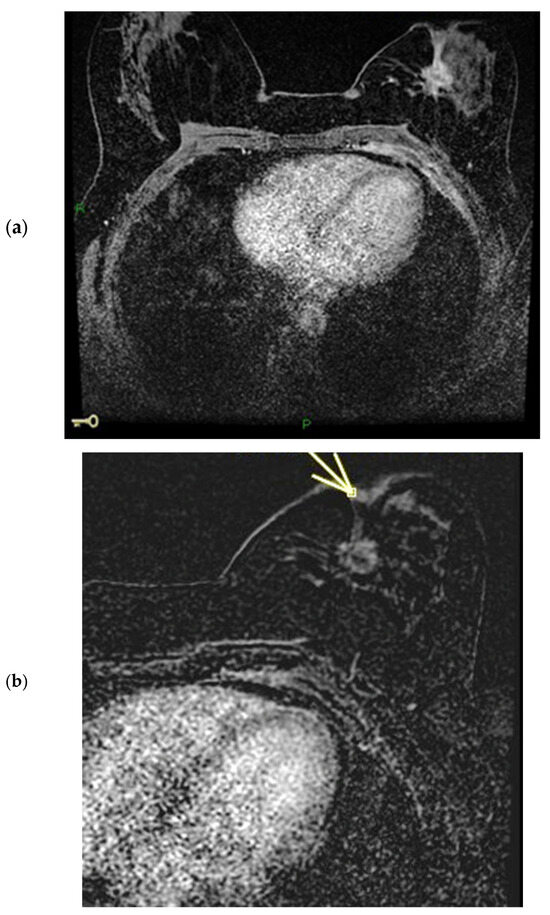

Figure 4.

(a,b) Patient’s name R.M. In the MIP (maximum-intensity projection) reconstruction of the first post-contrast fat-suppressed T1 sequence, we can observe a gross area of pathological enhancement, which affects the external quadrants of the left breast and infiltrates the nipple (a). During ce-MR, no SLE and no NEZ are present in the affected left breast nipple; the arrow indicates marked patchy nodular INE of the left breast nipple (b).

Figure 5.

(a,b) Patient’s name R.M. In the ce-CT scan, the arrow shows enhancement of the base of the left nipple alone (and not of the body).

Figure 6.

Patient’s name R.M. During PET/CT, the pathological NAC-SUV value is measured at the base of the left nipple.